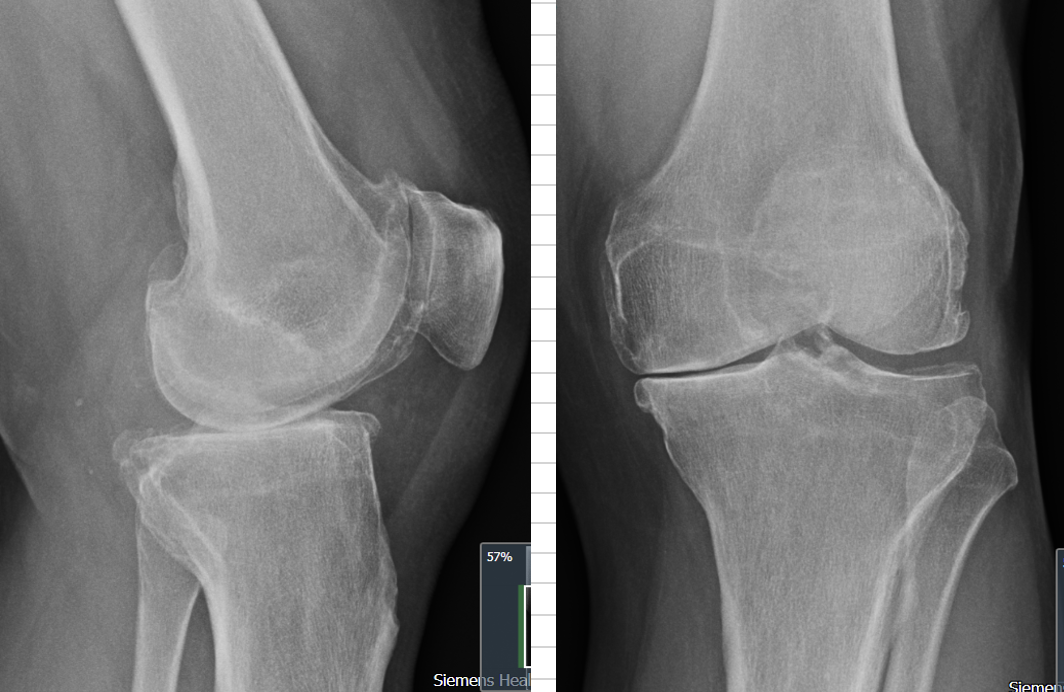

The image on the right is an AP (Antero-Posterior) view..

It looks at the knee from the front.

And on the outside of the knee..

The right hand side in that pic

There's good joint space.

Gap between tibia + femur

On the inside of the knee

The left hand side in that pic

The joint space has completely gone.

So called bone-on-bone osteoarthritis.

The image on the left is the lateral view

It looks at the knee from the side. And it shows:

The patellofemoral joint does not look too bad.

Under the kneecap is okay.

And the main point of cartilage loss is in the middle of the tibia (medial tibial plateau). In the middle of the knee.

The cartilage at the back of the knee (on the inside) is..

=> Intact

That means the ACL (Anterior Cruciate Ligament) is likely intact.

That's the ligament that provides front to back stability.

And the knee is suitable for a partial knee replacement.